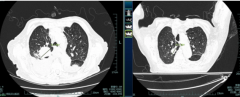

天龙八部sf提示右肺的占位性病變可能是罪魁禍首這是肺癌常見的并發癥之一

天龙八部sf精準早篩是要害。呼吸科副主任醫師張巖巍一針見血地說:對抗肺癌,早篩是最好武器!他深入淺出地講解了肺癌高危人群的精準評估與肺結節的鑒別要點,著重低劑量螺旋CT篩查是發...